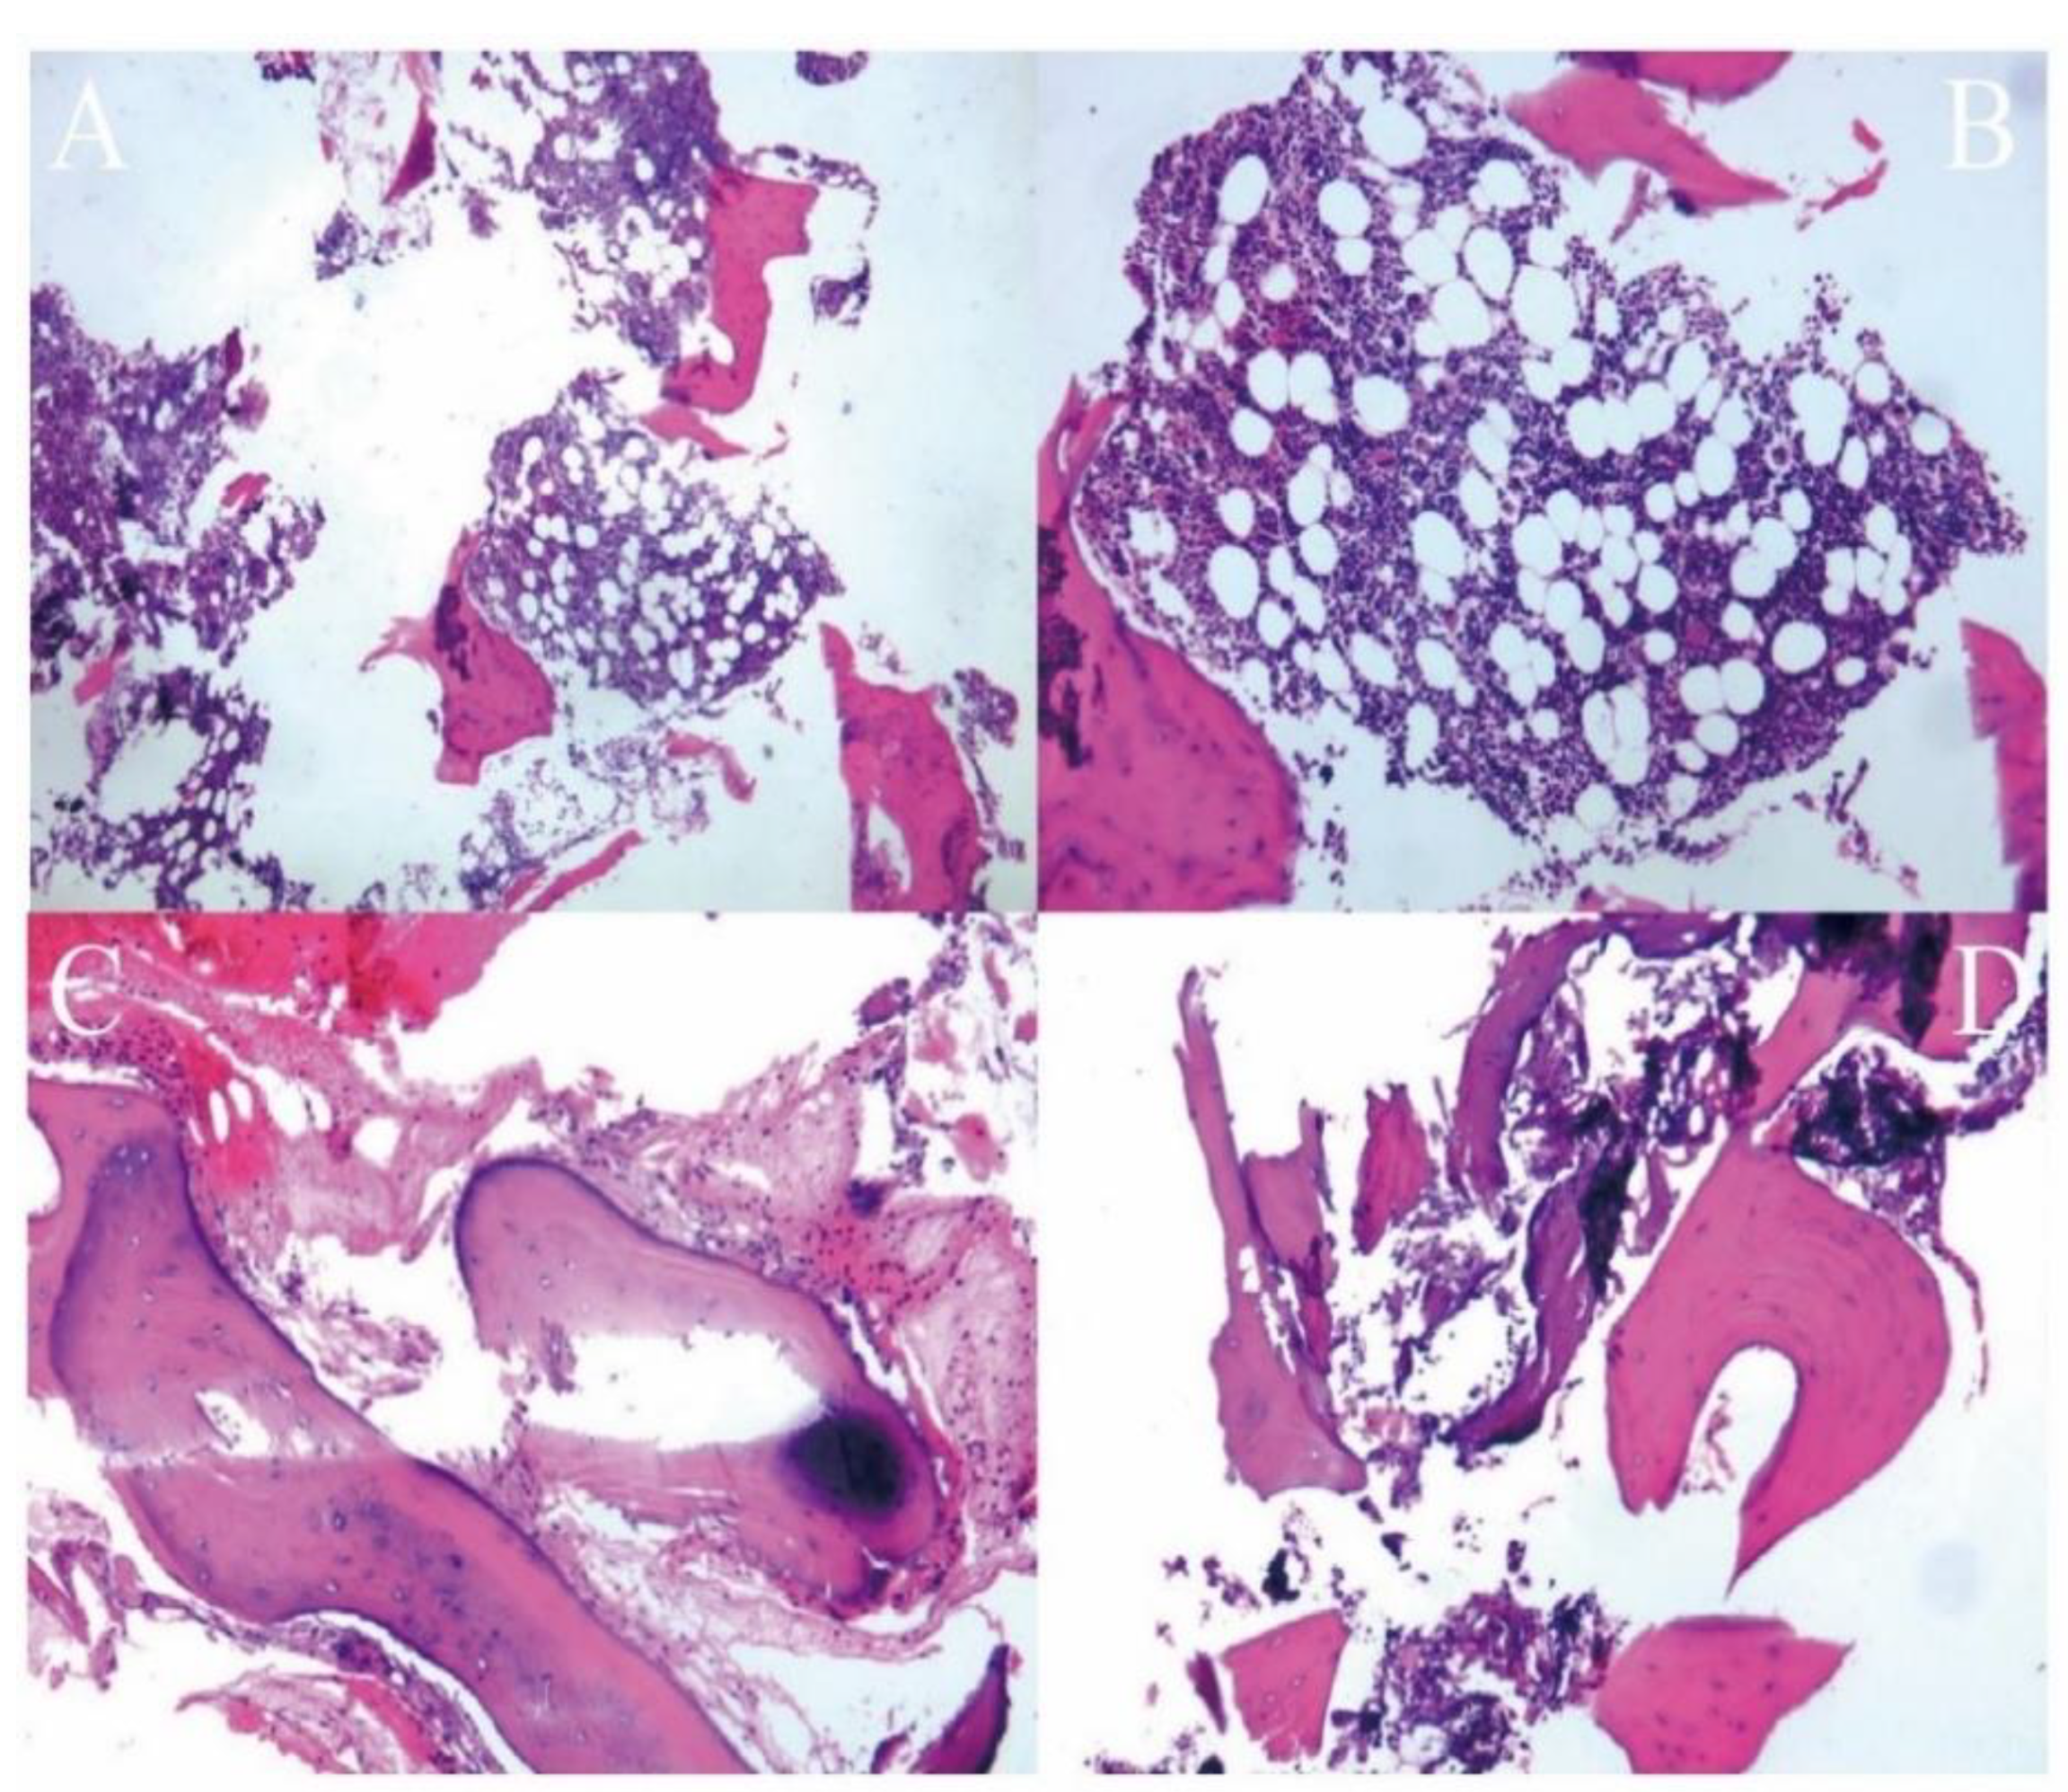

2.2.2. Surgical Procedure

3. Results